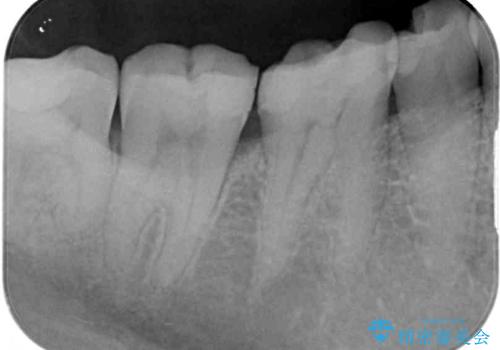

- 奥歯が欠けてしまったとのことで来院された患者様です。

おそらく歯が欠けて、装着されていた銀歯が外れてしまったと思われましたが、患者様はあまりはっきりとは覚えていないとのことでした。

咬合力が強いため、強化セラミッククラウンでの補綴治療を行うこととしました。